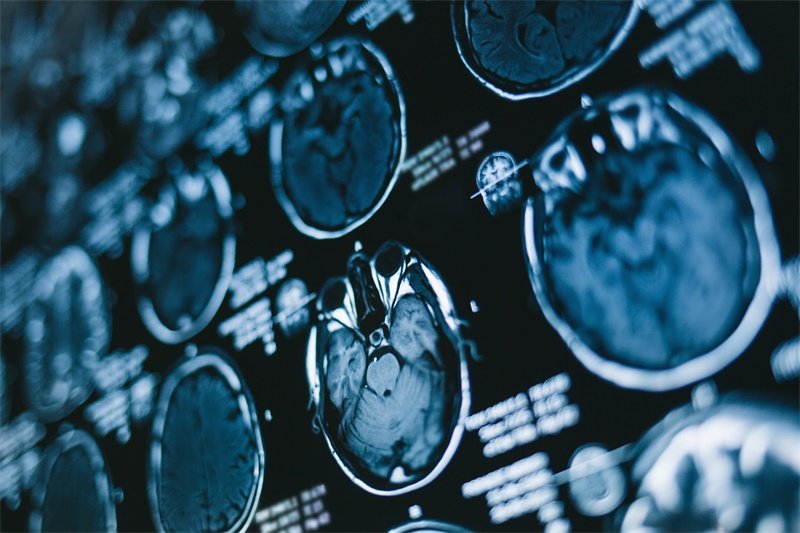

脑血管炸弹拆除记:为何有些 脑动静脉畸形(AVM) 让医生也如履薄冰?关键答案藏在畸形团的构型 致密型 与弥散型的天壤之别里! 一个边界清晰有望根治,一个浸润生长危机四伏。而 这直接决定...

确诊 脑动静脉畸形 后最令人窒息的恐惧,莫过于那颗深埋颅内的不定时炸弹 脑出血 !一旦破裂出血,半数以上预后不良,死亡率高达25%。有的虽保住了性命,但成为植物人。 怎么治? 开颅做...

在颅内深处潜伏着一枚不定时炸弹 脑动静脉畸形(AVM) ,它如同扭曲的血管迷宫,一旦破裂出血,半数患者将面临死亡或永久瘫痪的绝境。而当姑息治疗沦为风险赌局,及时选择全切手术,或许...